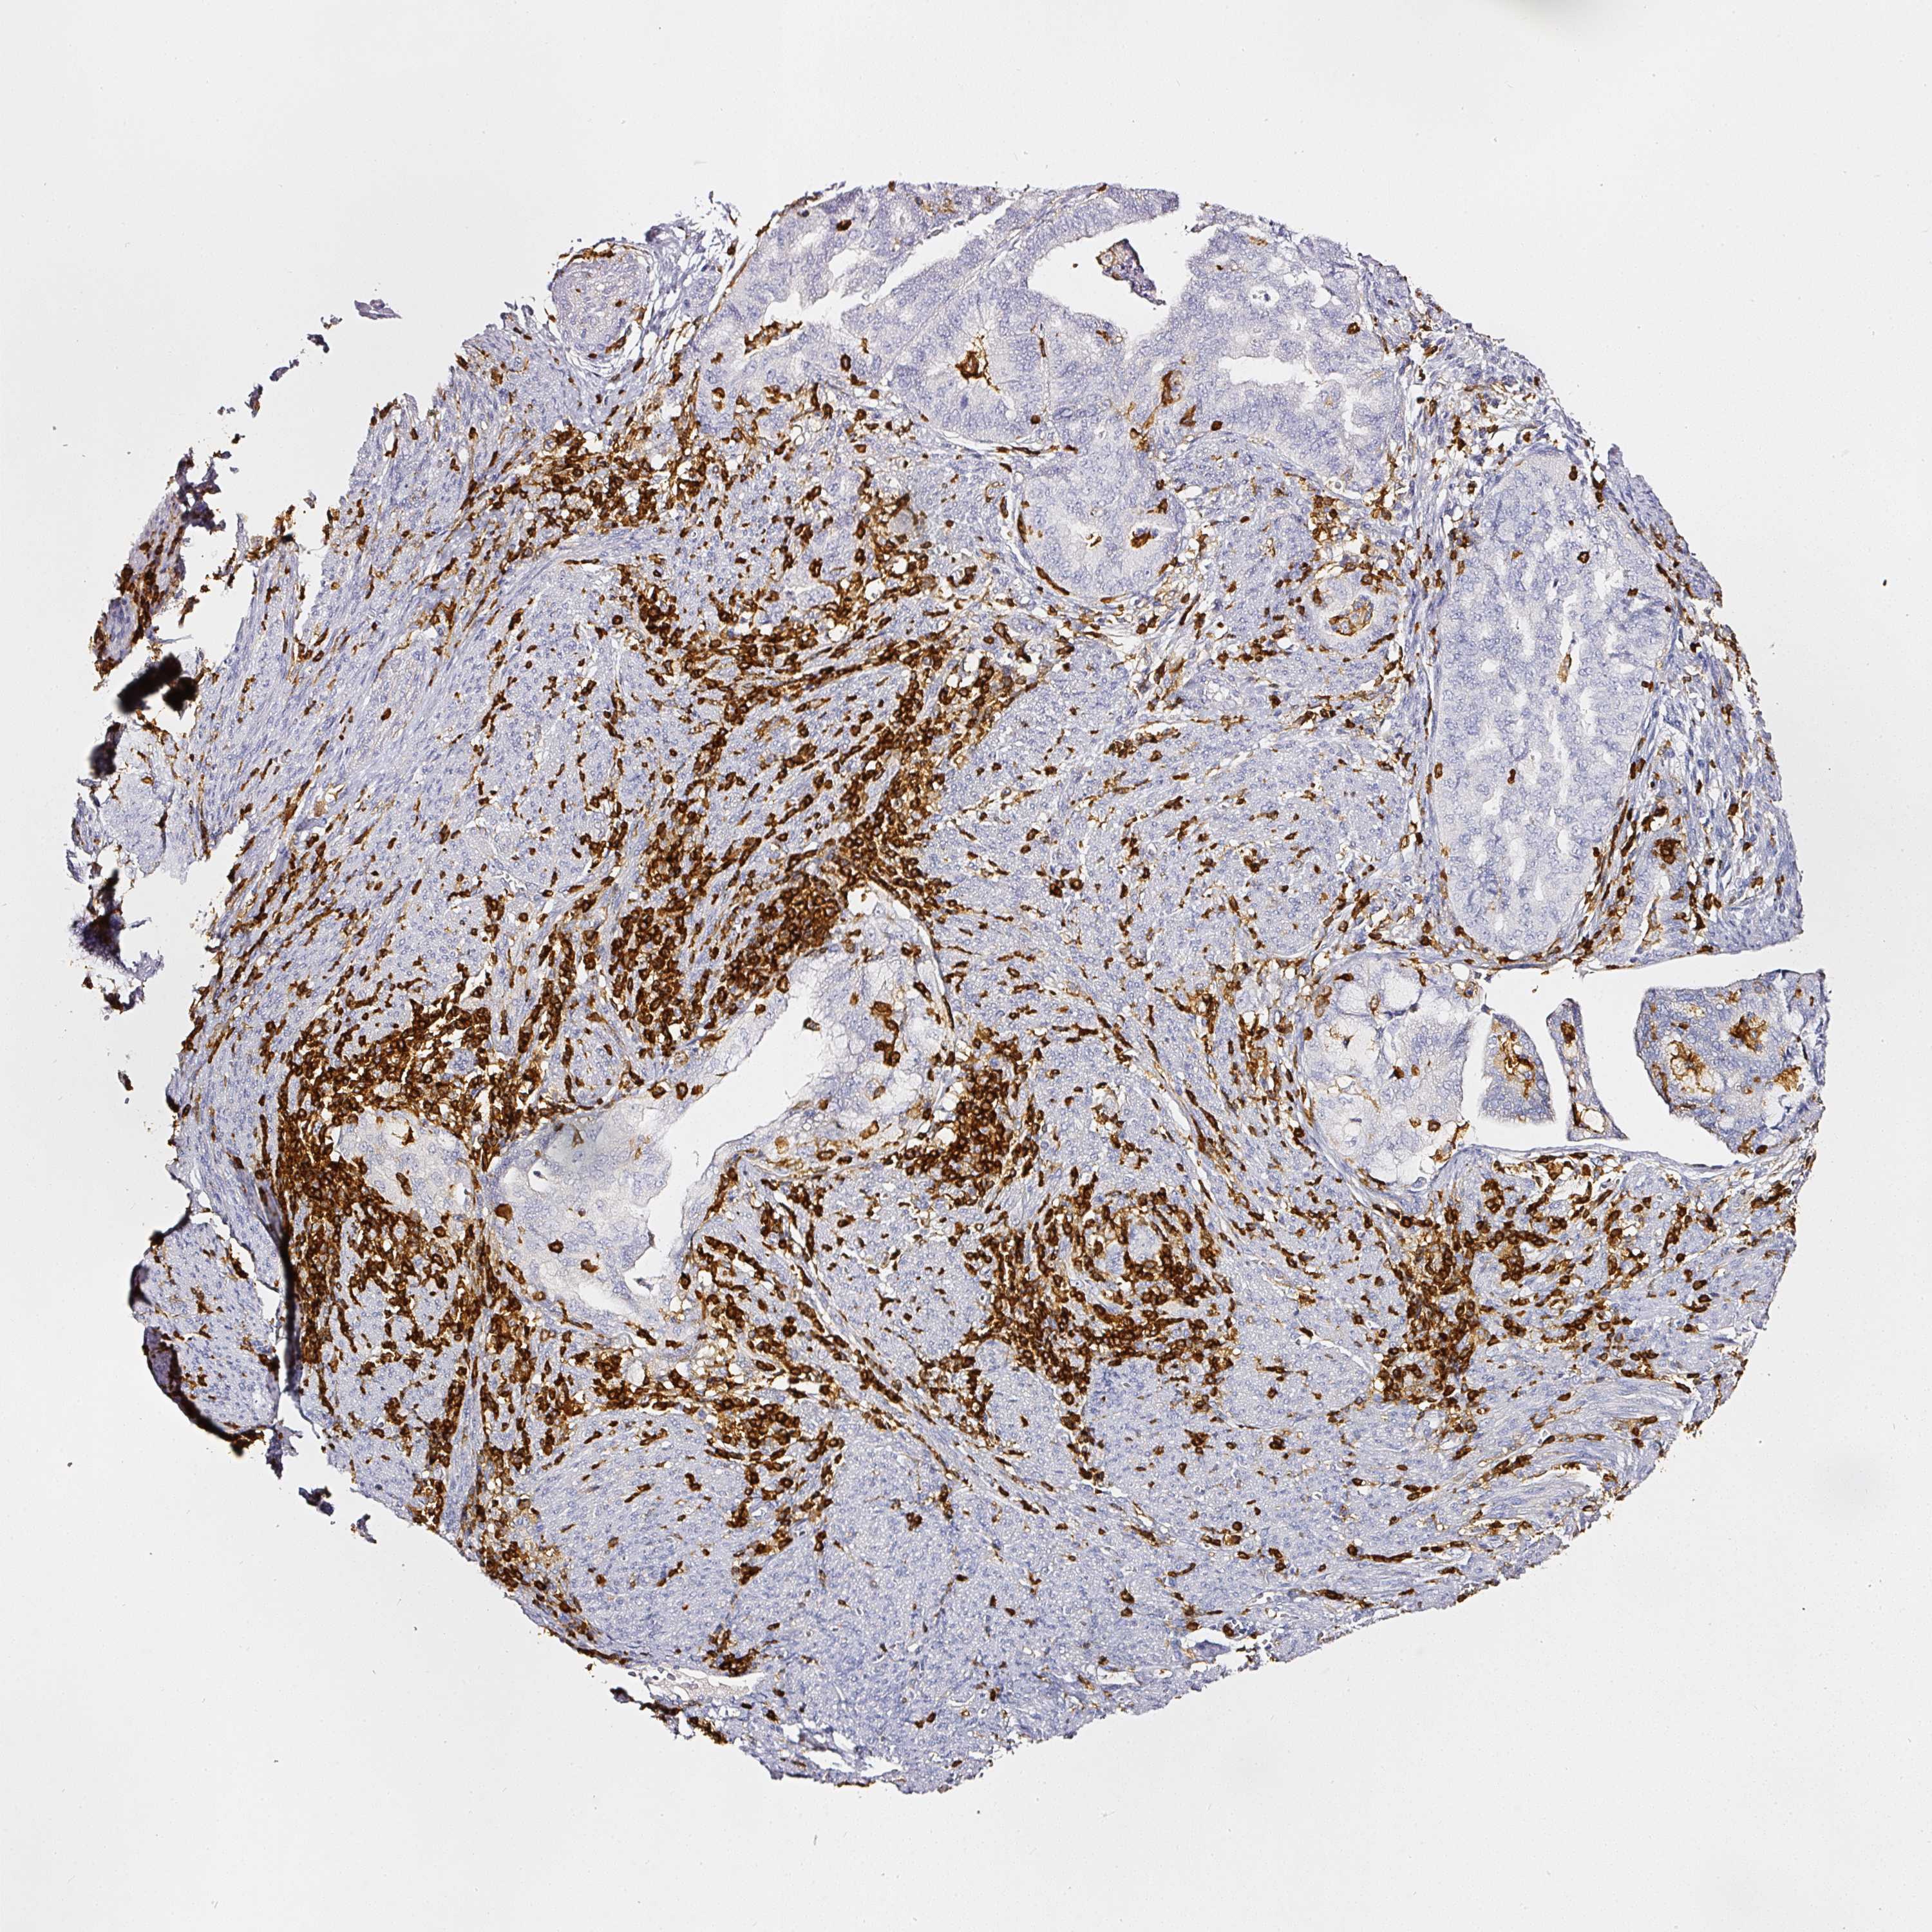

ENDOMETRIAL CANCER - Protein expressioni

A mouse-over function shows sample information and annotation data. Click on an image to view it in a full screen mode. Samples can be filtered based on level of antibody staining by selecting one or several of the following categories: high, medium, low and not detected. The assay and annotation is described here.

Note that samples used for immunohistochemistry by the Human Protein Atlas do not correspond to samples in the TCGA dataset.

Antibody stainingi

Antibody staining in the annotated cell types in the current human tissue is reported as not detected, low, medium, or high, based on conventional immunohistochemistry profiling in selected tissues. This score is based on the combination of the staining intensity and fraction of stained cells.

Each image is clickable and will lead to virtual microscopy that enables deeper exploration of all samples and also displays staining intensity scores, fraction scores and subcellular localization as well as patient and tissue information for each sample.

Antibody HPA018849

Antibody HPA019536

Antibody CAB033987

Staining

High

Medium

Low

Not detected

Intensity

Strong

Moderate

Weak

Negative

Quantity

>75%

75%-25%

<25%

None

Location

Nuclear

Cytoplasmic/membranous

Cytoplasmic/membranous,nuclear

Adenocarcinoma, NOS

Adenoma, NOS

Adenocarcinoma, metastatic, NOS